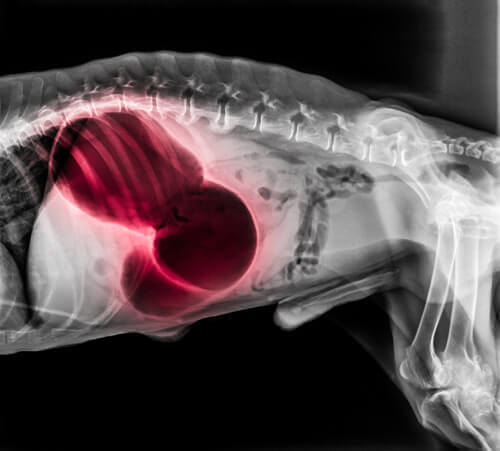

En av de främsta processerna inom cirkulationssystemet är förmågan att koagulera blod. Men när blodet koagulerar på fel plats och bildar blodproppar hos hundar kan de utgöra en allvarlig hälsorisk.

Koaguleringen är viktig för att sår ska kunna läkas och för att skador ska kunna repareas, både på huden och i de interna organen. Men det måste som sagt ske i rätt omständigheter.

Den främsta risken är att blodpropparna kan stoppa blodcirkulationen och därmed förhindra att syre når vävnaden i kroppen.

Man måste vara medveten om att en blodpropp kan leda till en stroke och andra akuta, livshotande tillstånd.

Blodproppar kan vara dödliga för hundar och du måste därför konsultera en veterinär direkt om du misstänker att hunden har drabbats, eftersom den kan vara i riskzonen för trombos.